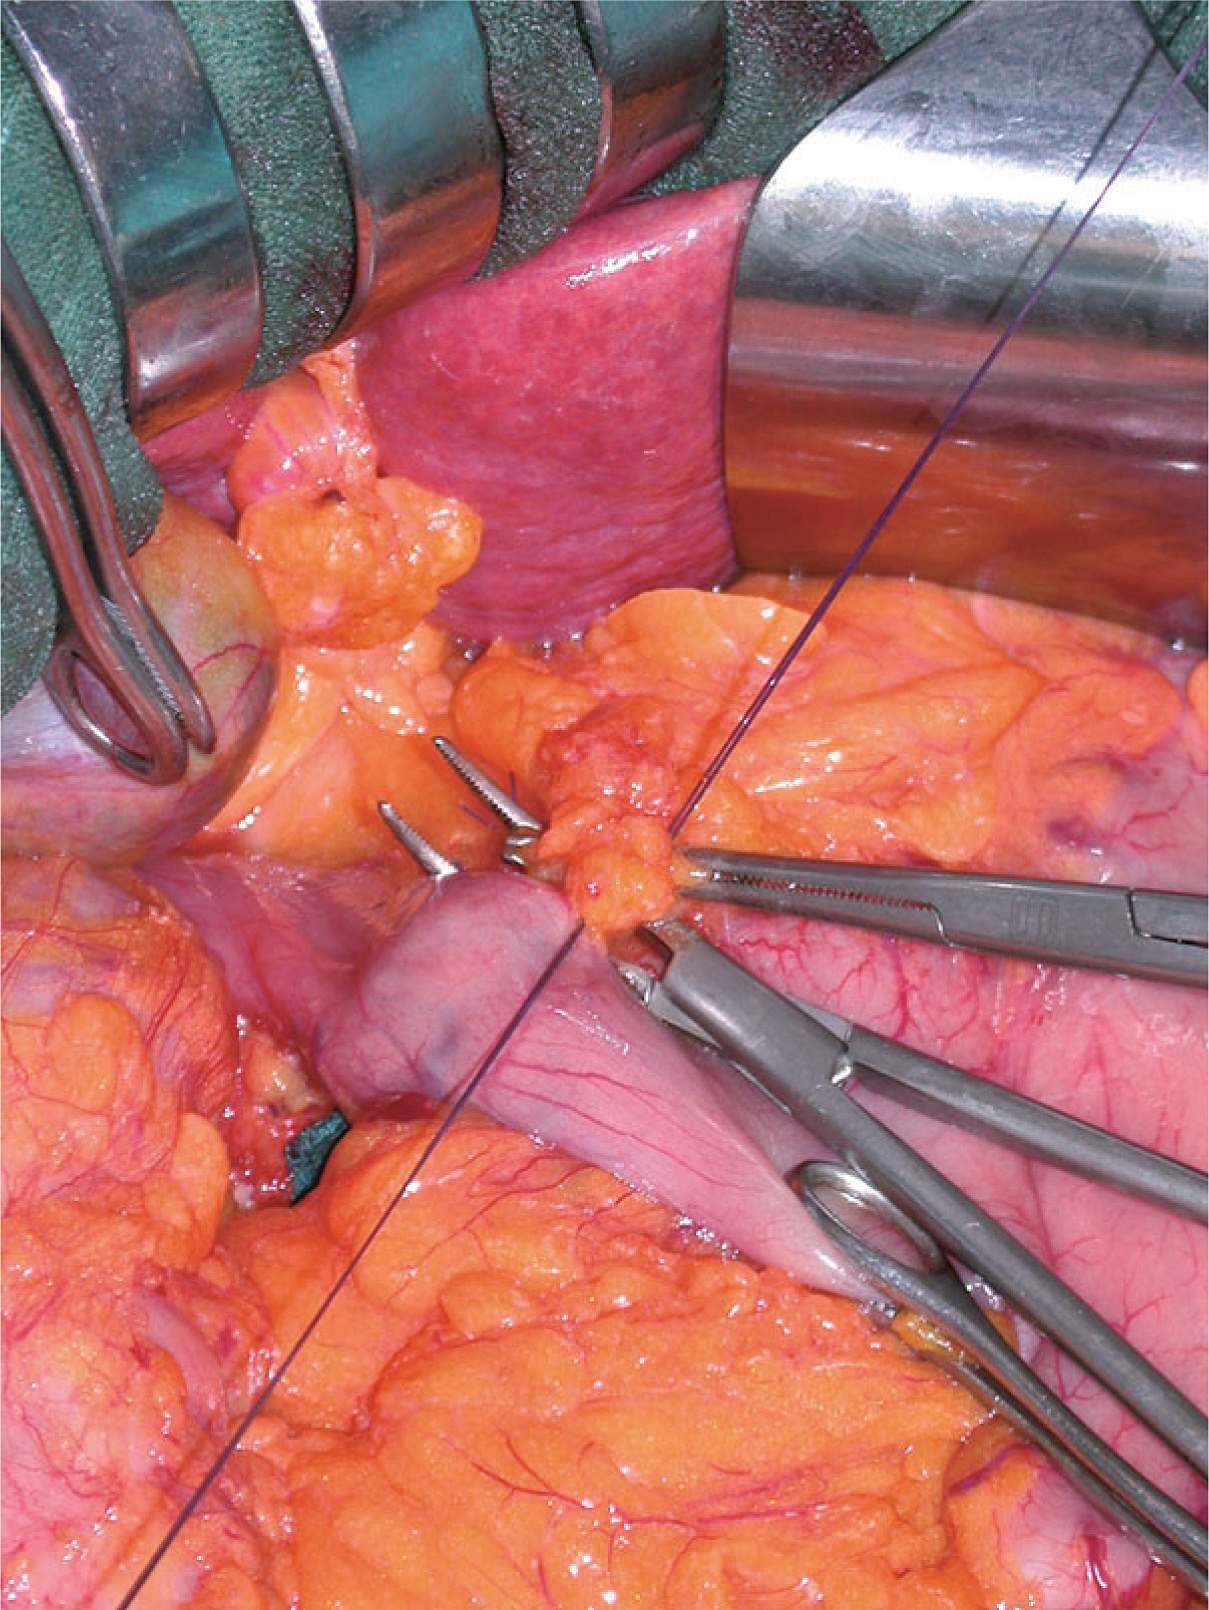

图2-34 紧张胃左血管,首先可见胃左静脉,于其根部结扎切断;胃左动脉即位于其头侧,于其根部结扎切断,保留侧双重结扎。

图2-35 图2-34示意图。

图2-36 结扎胃左动脉、静脉时,需小心可能存在的发自胃左动脉的副肝左动脉,这种变异的肝左动脉出现率为11.5%。术前CT扫描动脉成像可清楚显示变异的肝左动脉(红色箭头)。